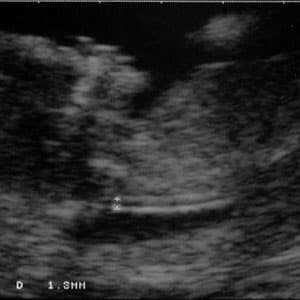

Độ mờ da gáy hay còn gọi là độ dầy da gáy hoặc khoảng sáng sau gáy là một đặc điểm hình thể trên siêu âm, do sự tích tụ dịch dưới lớp da phía sau cổ thai nhi trong quý đầu của thai kỳ. Đây là một tổ chức có tính chất sinh lý, được quan sát thấy ở tất cả thai nhi trong quý đầu của thai nghén ( từ 12-14 tuần ). Khoảng sáng sau gáy sẽ biến mất sau 14 tuần.

Siêu âm đo độ mờ da gáy thường được thực hiện vào tuần 11-14 của thai kỳ, chính xác nhất là tuần 12. Trước tuần thứ 11, kỹ thuật đo chưa chính xác và khó khăn vì bào thai còn quá nhỏ. Tuy nhiên, sau tuần thứ 14, da gáy sẽ trở về bình thường (không có nghĩa là thai bình thường) nên việc đo độ mờ da gáy không còn ý nghĩa. Do đó, thời điểm để đo độ mờ da gáy chính xác nhất là tuần 12-13 của thai kỳ. Mẹ bầu không nên bỏ lỡ thời điểm vàng này.

Kỹ thuật đo chủ yếu thực hiện qua siêu âm nhưng một số trường hợp đặc biệt cần tiến hành thêm chụp âm đạo cho người mẹ, để có kết quả chính xác. Không có bất kỳ nguy hiểm nào cho mẹ và thai nhi trong quá trình thao tác.